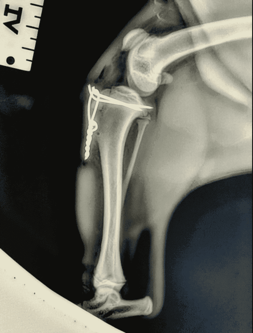

After discussion with the owners, we elected to proceed with surgery to repair the tibial crest avulsion (fracture). Given that we could do this surgery in the clinic, it did not require a referral to a specialist (like the pacemaker case above). The veterinary nurses assisted in preparing the patient for anaesthesia and preparing the surgical site – read our previous blog about anaesthesia in veterinary medicine.

The fracture was repaired with tension bands; see the x-ray attached. The implants will not be removed and will remain in the stifle. After rest and progressive controlled exercise, the fracture site will heal, and little Fred will return to running and playing in no time!

Images (X-rays) is Fred.